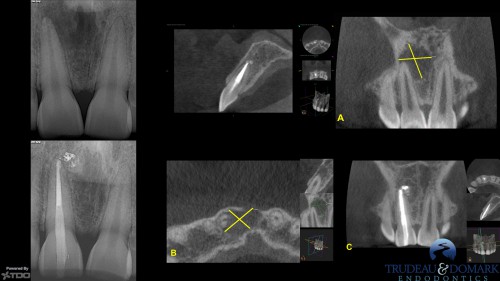

Pac Mac help? Trudeau? Anyone?

By JK / August 14, 2018

Hi Steve, Here are a couple of single-cone BC sealer cases from today, and last […]